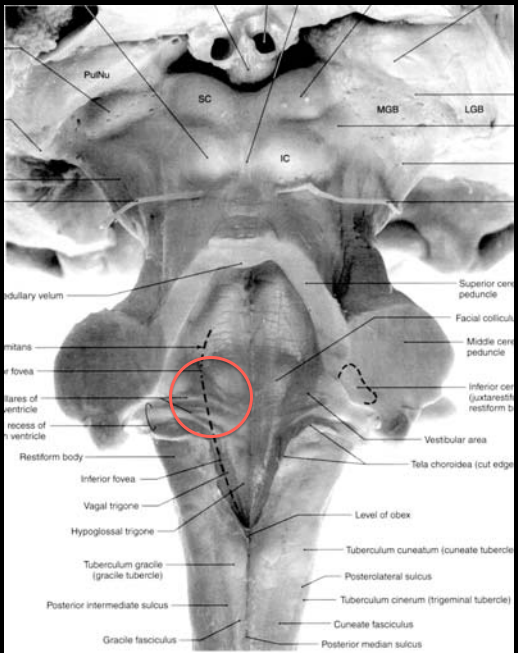

Trigeminal Motor Nucleus in the rostral pons, the origin of the branchial motor fibers of CN V3, which innervate the muscles of mastication

Solitary nucleus in the rostral medulla; the origin of the special (visceral) sensory fibers of CN VII (gustatory), which innervate the anterior 2/3 of the tongue.

Facial motor nucleus, origin of the branchial motor (special visceral) fibers of CN VII that innervate all the muscles of facial expression, stapedius m., stylohyoid m., and posterior belly of the digastric m.

Cochlear nucleus (CN 8)